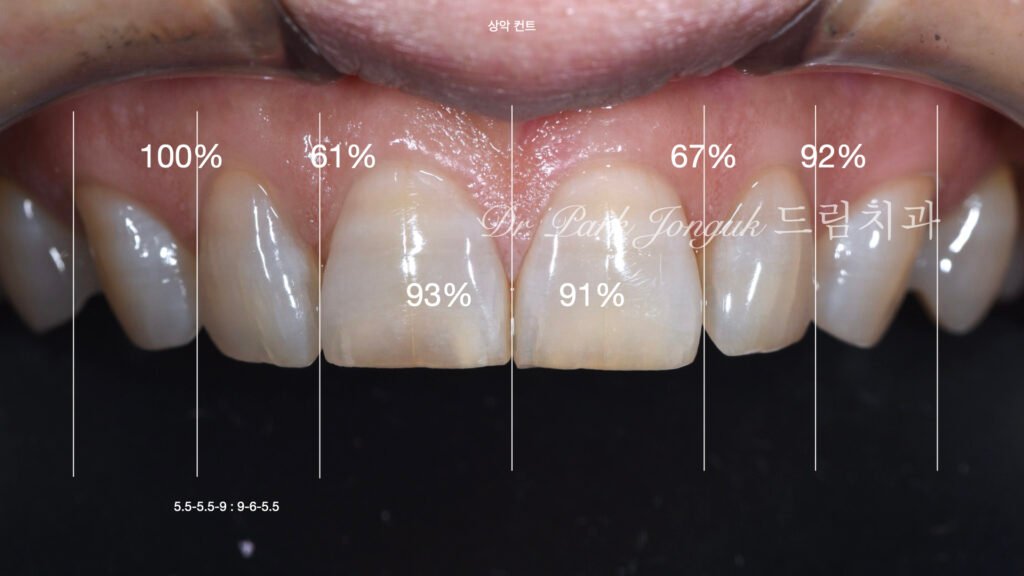

- 상악 중절치의 폭이 측절치 대비 약 1.5~1.6:1 비율로 시각적 불균형

- 교합 마모로 인한 치아 길이 감소, 이로 인한 폭-길이 비율 왜곡

2단계: 치아 간 비율 분석 각 치아의 실측 치수를 측정하고 이상적 비율과 비교했습니다. 이 환자의 경우:

- 중절치 폭: 평균 대비 정상 범위

- 측절치 폭: 평균 대비 약간 작음

- 중절치:측절치 비율: 1.5-1.6:1 (이상적 범위 1.4:1과 큰 차이)

- 치아 폭-길이 비율: 90% (이상적 80-85%보다 높음, 즉 너무 정사각형)